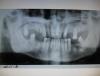

olala17 Опубликовано 31 мая, 2008 Поделиться Опубликовано 31 мая, 2008 Пациент,44 года,мужчина обратился с целью предстоящего протезирования;на обзорной рентгенограмме,прицельной и р.в боковой проекции в области удаленных 46,47 получилось вот что Ссылка на комментарий

annda Опубликовано 1 июня, 2008 Поделиться Опубликовано 1 июня, 2008 На КТ его.От неполного удаления(что,правда,сомнительно) до онкологии исключать. Ссылка на комментарий

olala17 Опубликовано 1 июня, 2008 Автор Поделиться Опубликовано 1 июня, 2008 На КТ его.От неполного удаления(что,правда,сомнительно) до онкологии исключать.Со слов пациента зубы удалены примерно 10 лет назад,жалоб нет,изменений конфигураций лица,нижней челюсти нет,теперь проблема,чтобы отправить пациента для дальнейшей диагностики (в Моники)в направление надо написать предварительный диагноз,а какой "бог его знает" вот и ломаю голову Ссылка на комментарий

Никсон Опубликовано 1 июня, 2008 Поделиться Опубликовано 1 июня, 2008 Со слов пациента зубы удалены примерно 10 лет назад,жалоб нет,изменений конфигураций лица,нижней челюсти нет,теперь проблема,чтобы отправить пациента для дальнейшей диагностики (в Моники)в направление надо написать предварительный диагноз,а какой "бог его знает" вот и ломаю голову Я бы рекомендовал Вам в направлении поставить диагноз: конденсирующий остеит. Даже, несмотря на то что, причина( зубы) остеита отсутствует - диагноз абсолютно правомерен. Склеротические изменения в кости обусловлены ранее проходившими в этой области воспалительными процессами с "несколько иными результатами" - склероз костной ткани. Какого то специфического лечения данное состояние не требует. А Остеобластокластома (гигантоклеточная опухоль, остеокластома, гигантома) - это нечто другое.... Ссылка на комментарий

Никсон Опубликовано 1 июня, 2008 Поделиться Опубликовано 1 июня, 2008 спасибо...и мне казалось остеокластомы чаще на длинных трубчатых костях бывают Абсолютно. 10% примерно еще и челюсть(нижнюю) поражает. И болят. Но ночные боли для пораженной остеобластомой челюсти не характерны. Рентгенологическая картина несколько иная чем представленная Вами. Ссылка на комментарий

olala17 Опубликовано 1 июня, 2008 Автор Поделиться Опубликовано 1 июня, 2008 Абсолютно. 10% примерно еще и челюсть(нижнюю) поражает. И болят. Но ночные боли для пораженной остеобластомой челюсти не характерны. Рентгенологическая картина несколько иная чем представленная Вами.естьь предположение(по мнению моей коллеги) пусть и не совсем похоже"гигантоформная цементома" хотя они чаще всего связаны с зубами,а в этом случае они вообще отсутствуют Ссылка на комментарий